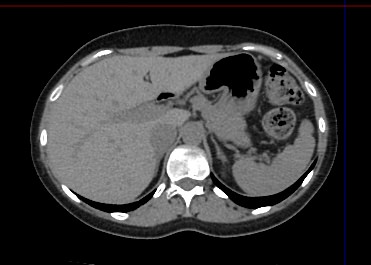

Современным высокоинформативным способом выявления патологических изменений поджелудочной железы является мультиспиральная компьютерная томография с прицельным сканированием органа.

Диагностика заболеваний поджелудочной железы в нашей клинике проводится на современном мультиспиральном компьютерном томографе экспертного класса TOSHIBA AQUILION CXL. Аппарат производит послойное сканирование исследуемой зоны. Увеличенное количество детекторов, которыми оснащен томограф, дает возможность проводить исследование за короткий промежуток времени, что позволяет значительно снизить лучевую нагрузку на организм пациента.

При помощи специальных цифровых приложений данные, полученные при сканировании, преобразуются в трехмерные изображения органа, что дополнительно повышает точность и достоверность диагностики заболеваний поджелудочной железы.

Контрастирование позволяет отличить зоны воспаления, деструкции, разрастания фиброзной ткани и опухолевой трансформации от сохраненной паренхимы поджелудочной железы. КТ поджелудочной железы с контрастированием дает исчерпывающую информацию о состоянии органа и патологических процессах в нем.